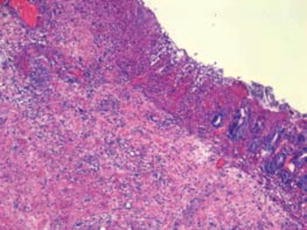

Fig. 1

Fig. 2

Fig. 3

Fig. 4

Fig. 5

Fig. 6

Fig. 7

Fig. 8

Fig. 9